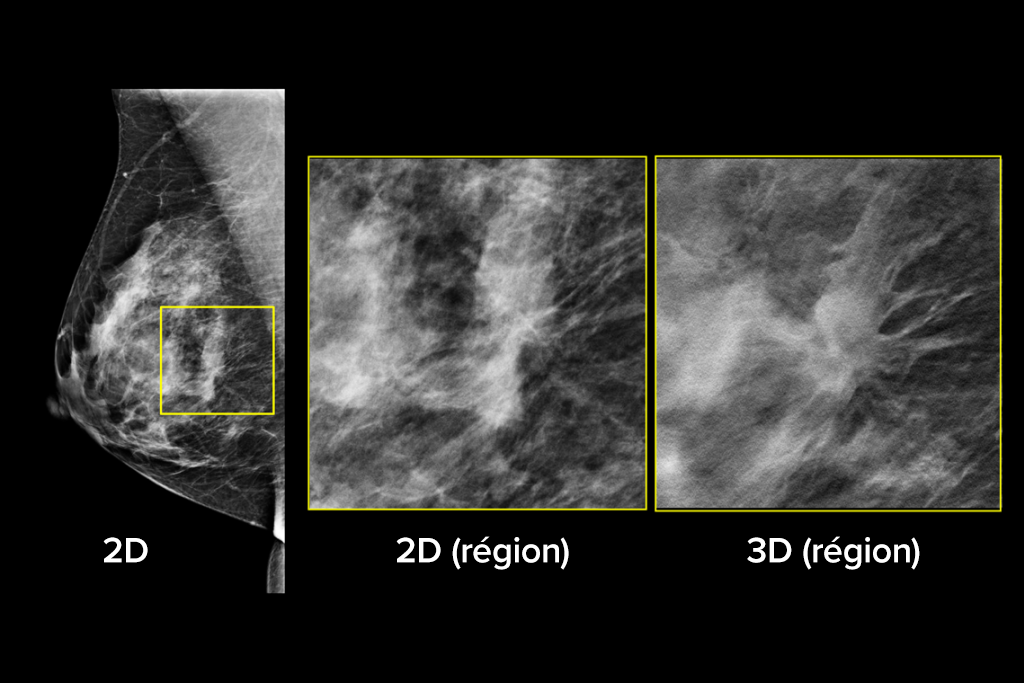

Images cliniques

Images cliniques d’une mammographie

Images cliniques d’une mammographie avec lésion suspecte

Images cliniques d’une mammographie sur un sein graisseux